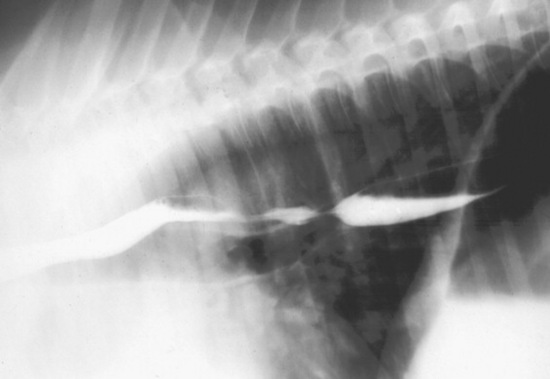

Abdominal radiography is useful to evaluate the small and large intestines for sand accumulation, enterolithiasis, impactions, or small intestinal disorders in foals. When sand is ingested, it generally will accumulate within the large colon along the ventral abdomen8 (Fig. 32-4). Radiography has been found to be a useful method to monitor the resolution of sand impactions after medical management; however, sequential examinations are needed to verify that the volume of sand has reduced.8 If the volume of sand is large enough, it is difficult to determine if an enterolith is present because of summation of the two lesions. Enteroliths are a solid concretion of mineral that usually forms around a nidus, such as a metallic foreign body (Fig. 32-5). The mineral composition is varied, as illustrated by the different opacities present within the enterolith. Radiographs have a 96.4% positive predictive value to detect enteroliths in high-prevalence areas. These enteroliths were generally found to be within the midabdominal radiograph, and 67% of small colon enteroliths caused large colon distention, which was also identified on radiographs.7 Impactions are more difficult to diagnose because usually there is just increased feed accumulation within the abdomen. Although no enterolith or obstruction is identified, granular material can be seen, usually within the ventral colon near the sternal flexure. This is because pelvic flexure impactions will cause the feed material to accumulate orad, causing distention of the left ventral colon (Fig. 32-6). Intestinal disorders such as functional ileus secondary to enteritis (Fig. 32-7) or obstruction secondary to intussusception or meconium impaction (Fig. 32-8) in foals can also be identified on abdominal radiographs. These images show large dilation of the small intestine, and differentiation between functional and mechanical ileus in foals is generally based on the size of the intestine and the volume of gas that is present.9 Evaluation of the abdomen using ultrasound may aid in qualifying the small or large intestinal motility as well as identifying the source of an obstruction if the determination on radiographs cannot be made.

image

Fig. 32-5 Radiograph of enterolith obtained after surgical removal from the small colon. Note the variation in opacities caused by the various types of mineral that are contained within the enterolith.